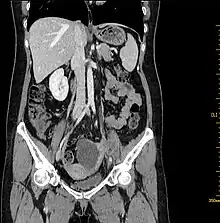

Computed tomography

Abdominal CT. Cystic solid mass was detected on the left adnexal and the solid components were enhanced[5]

Computed tomography (CT) scans is a diagnostic x-ray procedure that generates detailed cross-sectional images of the body, facilitating the detection of potential ovarian cancer spread to other organs.[16] While CT scans may not effectively visualize small ovarian tumors, they have the capability to detect larger tumors and evaluate their potential invasion into nearby structures. Additionally, CT scans can identify enlarged lymph nodes, signs of cancer spreading to the liver or other organs, and indications of an ovarian tumor impacting the kidneys or bladder. Although CT scans are not commonly used for biopsying ovarian tumors, they can be utilized in the biopsy of suspected metastases through a technique known as CT-guided needle biopsy.[16]